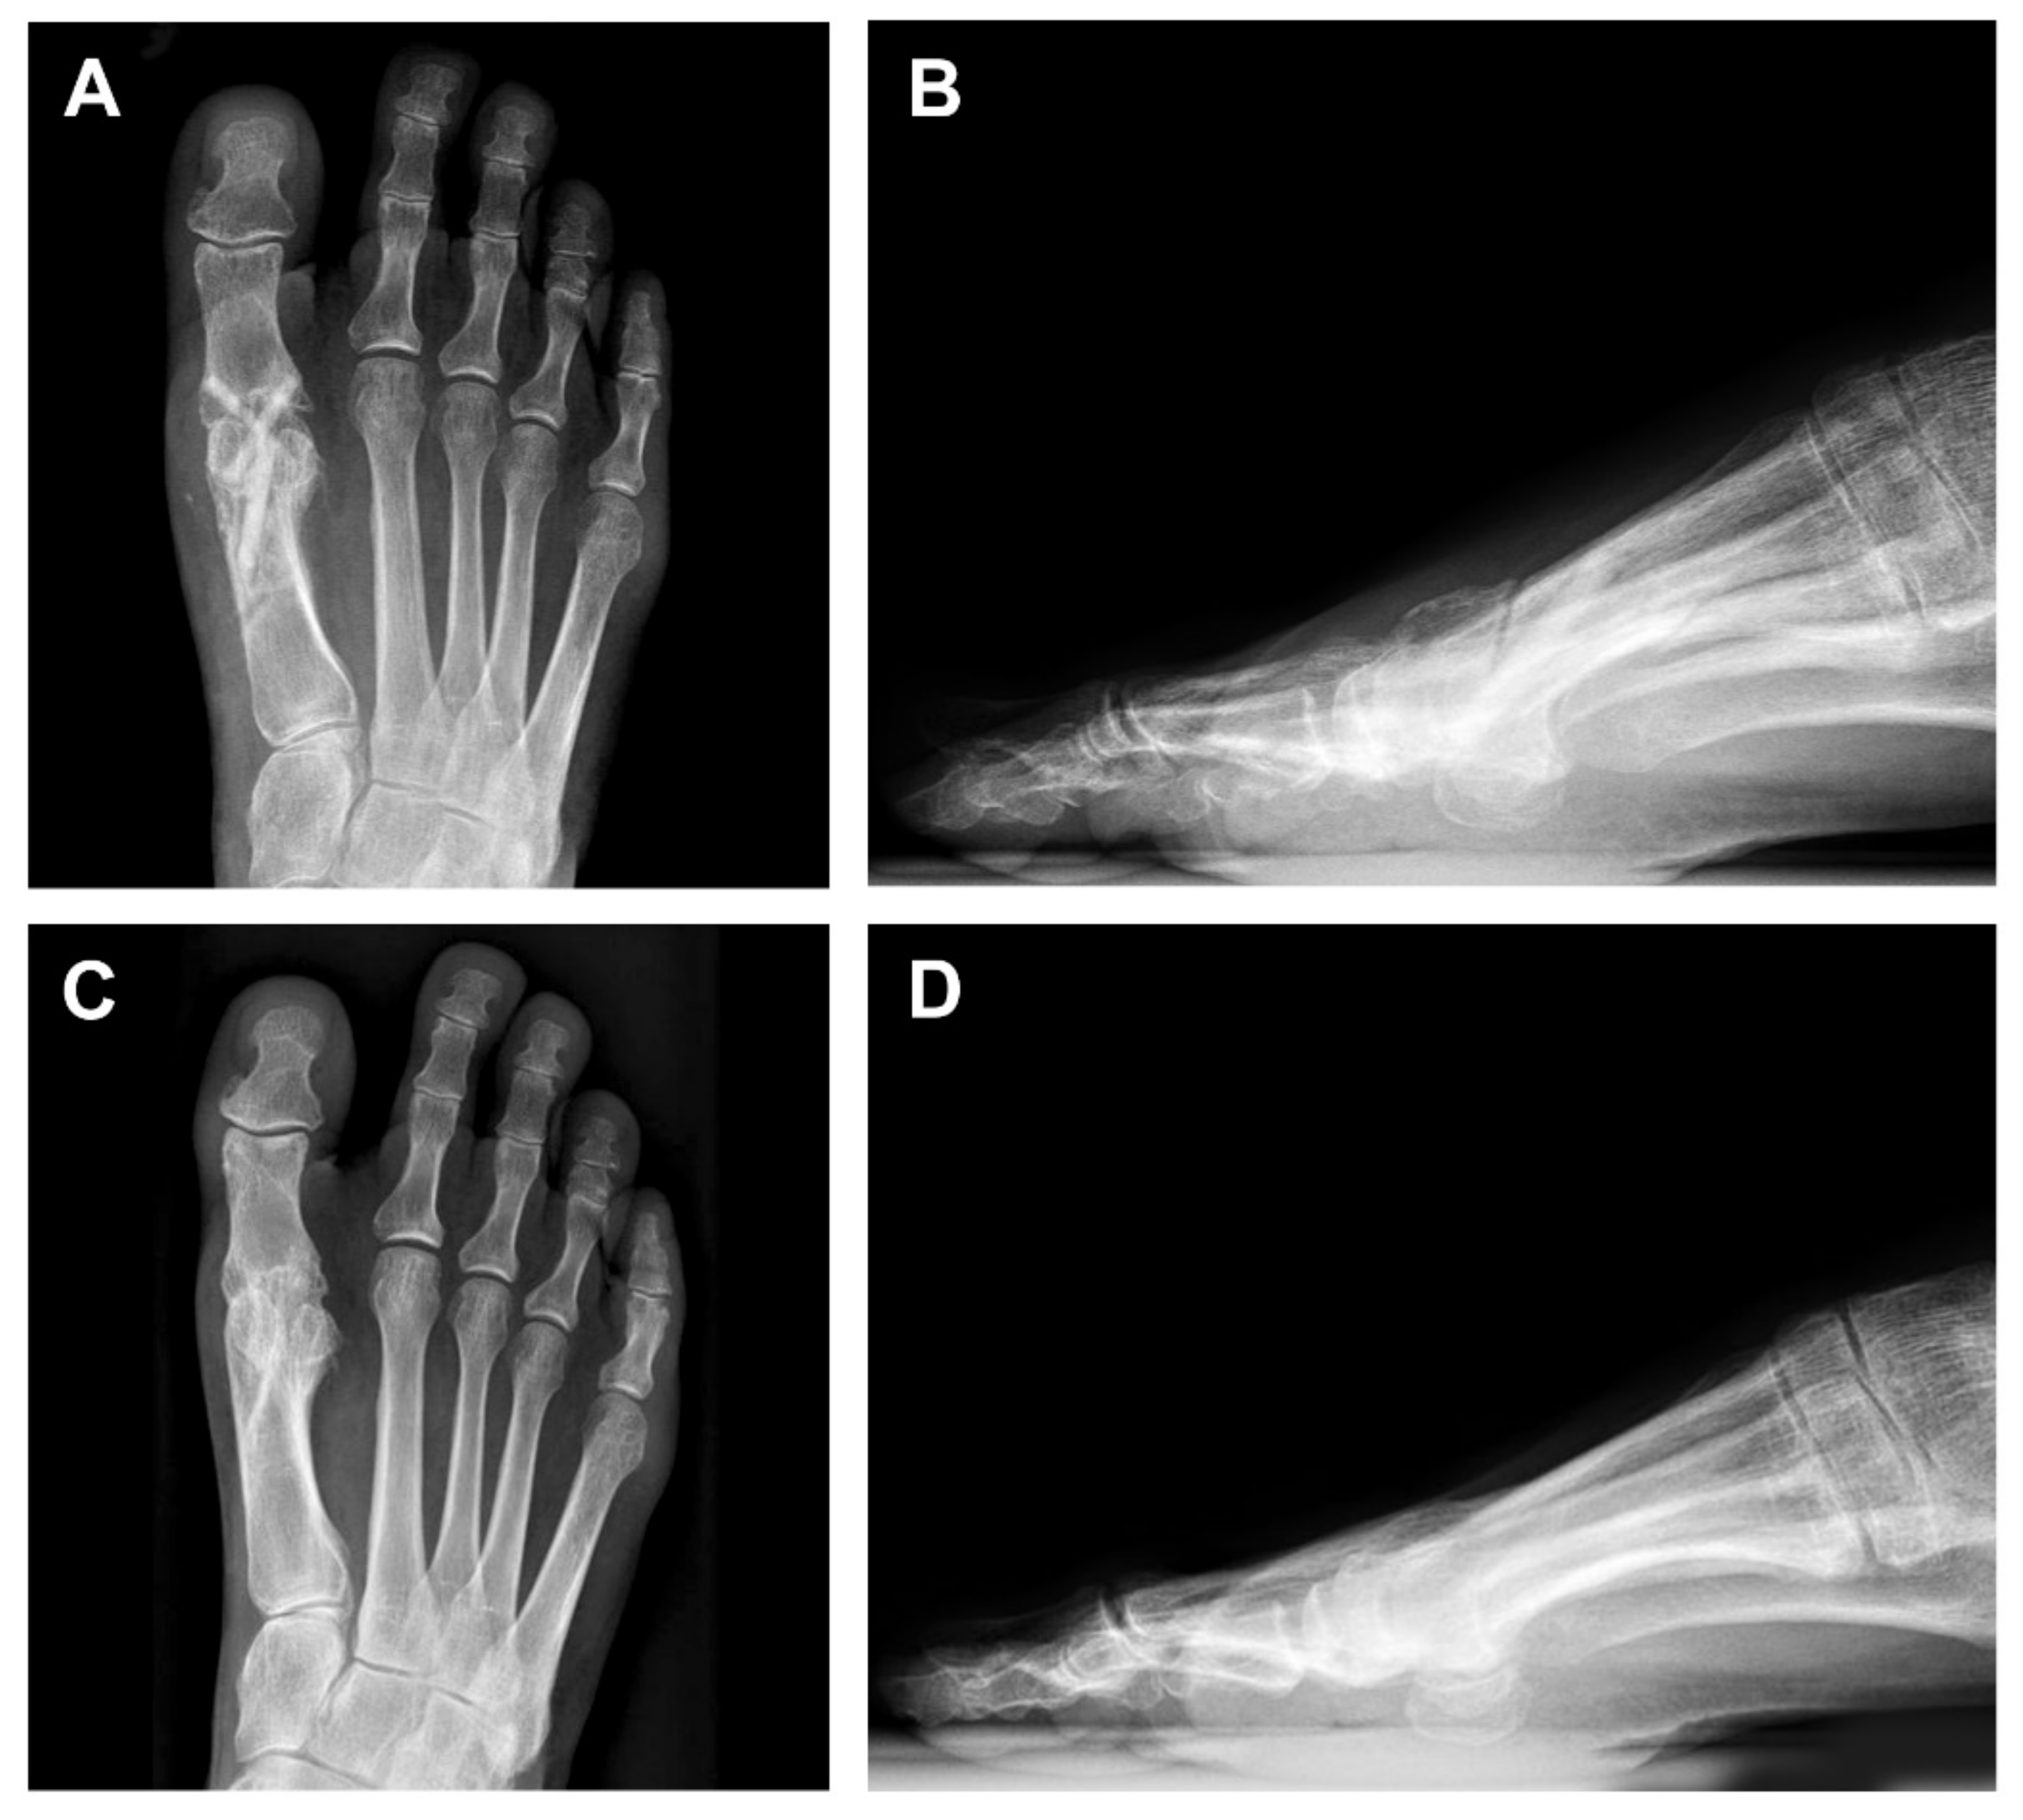

3. Case Presentation